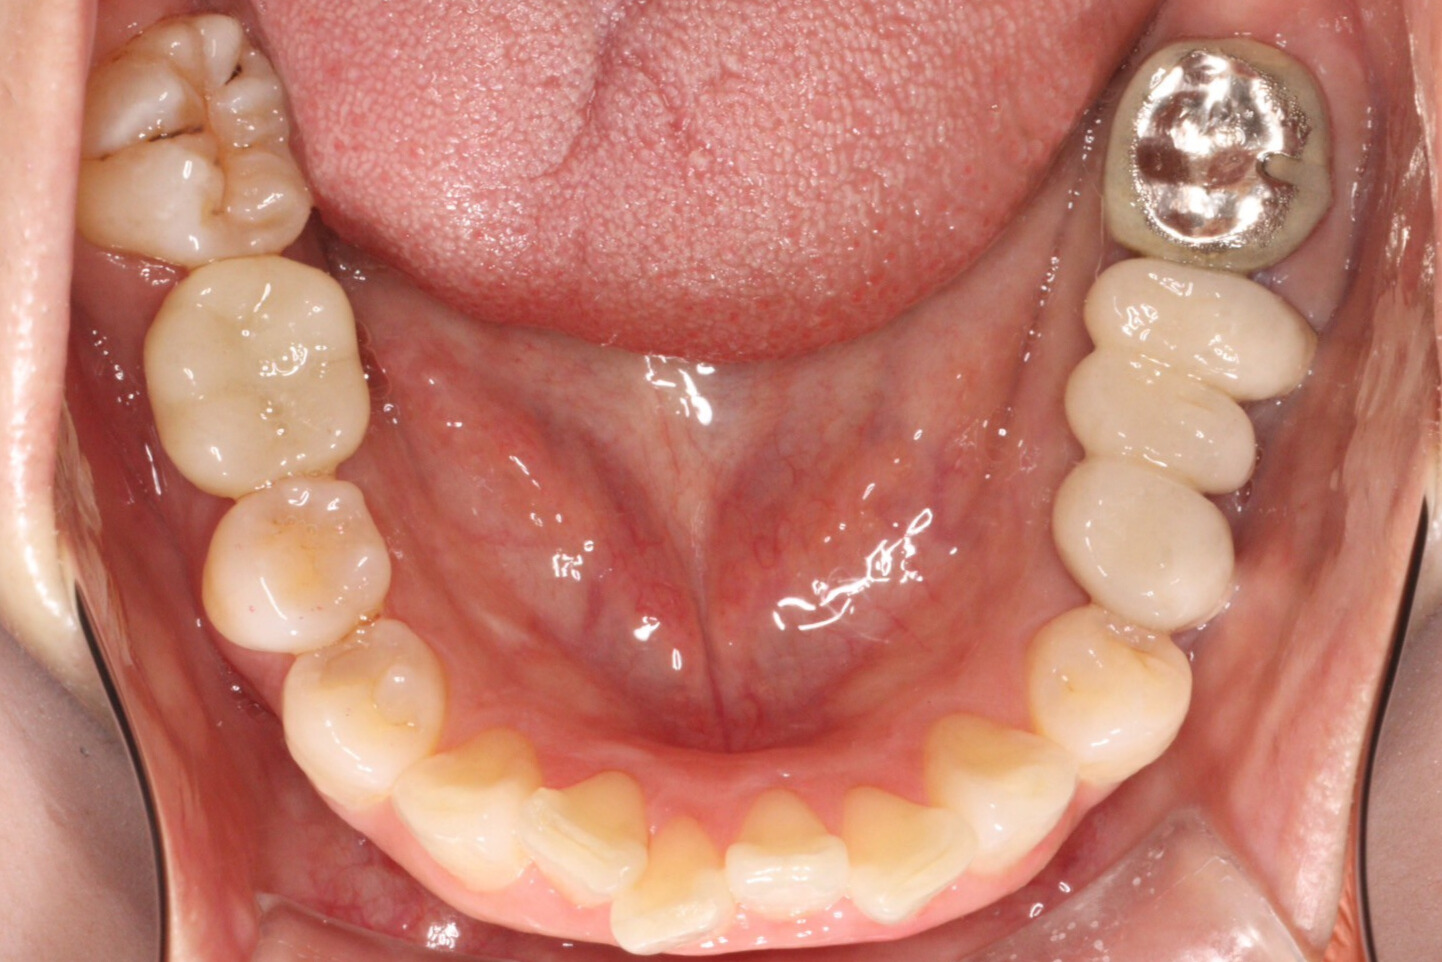

治療後

治療内容 | 右下の歯の根にヒビが入っていたため(歯根破折)抜歯を行い、抜歯後は歯ぐきの回復を待ち、インプラントを埋入しました。 オペ後2ヶ月間は経過を観察し、仮歯の期間を経て、最終的な被せ物をセットしています。 |